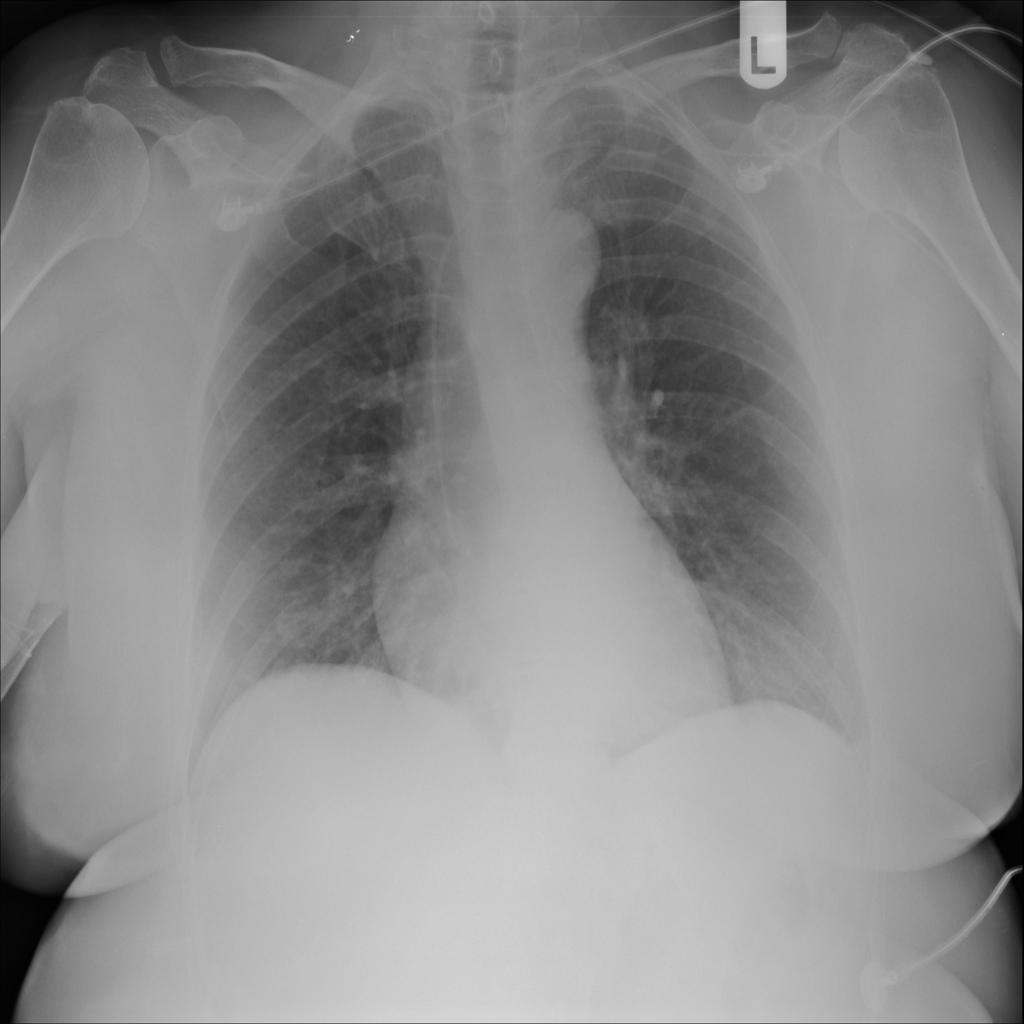

PAT-5B86 · IMG-009Edema

PAT-5B86 · IMG-009

PA